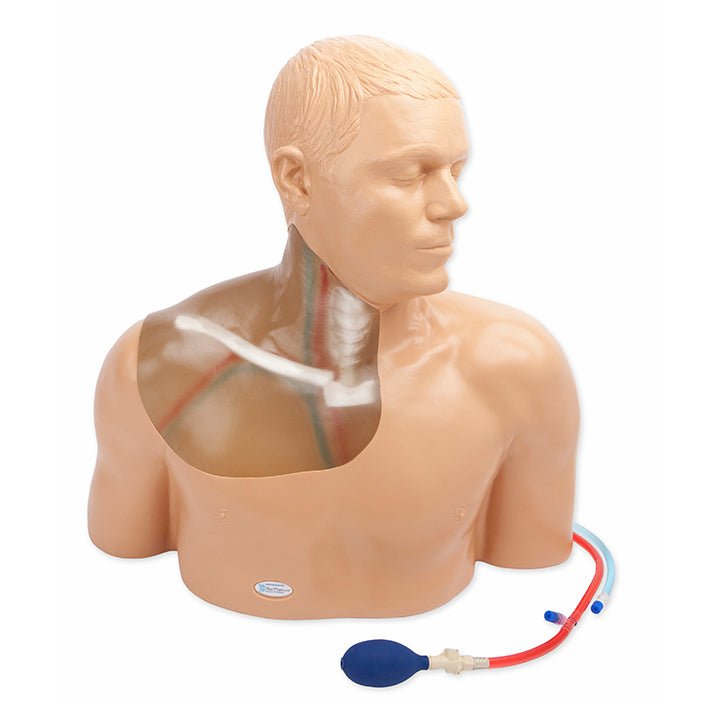

Gen II Ultrasound Central Line Model with Transparent Insert

Each model offers anatomically correct vascular anatomy of the right upper thorax and neck including the internal

jugular vein, brachiocephalic vein, subclavian vein, axillary vein, carotid artery, subclavian artery, and axillary

artery, as well as anatomical landmarks including the clavicle, the two heads of the sternocleidomastoid muscle, and the

sternal notch. Users can utilize traditional anatomical landmarks for blind insertion techniques, or utilize ultrasound

to obtain images of anatomical structures. A simulated SVC accommodates full threading of guidewires, dilators and

central line catheter placement. Venous and arterial fluids that are removed during central catheter insertions training

are easily refilled using quick fill ports. Users can run intravenous fluid for constant refill of vessels during

training.

Brand New! 2nd Generation upper torso ultrasound guided central line placement training model with transparent tissue insert allows users to develop and practice the skills necessary to gain proficiency in using ultrasound to guide central catheter insertions in the internal jugular vein (IJ), subclavian vein, and axillary vein while revealing the venous and arterial vessels as well as accessory boney structures. Developed with the goal of helping clinicians bridge the learning gap by allowing them to see the internal anatomical structures with their eyes as well as with ultrasound imaging, our transparent central line placement tissue offers superb ultrasound hands-on training. Using Blue Phantom proprietary simulated human tissue, this very realistic and ultra-durable transparent central venous access ultrasound training model is excellent for training clinicians in the psychomotor skills associated with ultrasound guided central line placement procedures. These ultrasound imaging skills include; using ultrasound system controls, transducer positioning and movement, recognition of arterial and venous anatomy, using ultrasound to target the appropriate vessels for cannulation, and performing a central venous access procedure.Helps

clinicians bridge the learning gap by allowing them to see the internal anatomical structures with their eyes as

well as with ultrasound imaging.

- Contains anatomically correct vascular anatomy of the right upper thorax and neck including the internal jugular vein, brachiocephalic vein, subclavian vein, axillary vein, carotid artery, subclavian artery, and axillary artery, as well as anatomical landmarks including the clavicle, the two heads of the sternocleidomastoid muscle, and the sternal notch

- Contains anatomically correct vascular anatomy of the right upper thorax and neck including the internal jugular vein, brachiocephalic vein, subclavian vein, axillary vein, carotid artery, subclavian artery, and axillary artery, as well as anatomical landmarks including the clavicle, the two heads of the sternocleidomastoid muscle, and the sternal notch